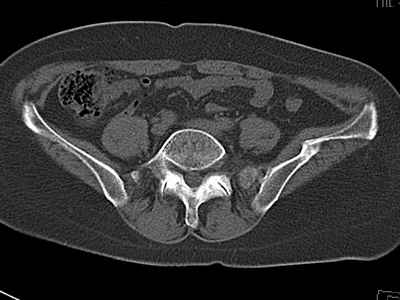

Уважаемые коллеги, возник вопрос по лечению нашей пациентки 60 лет. Около года назад множественная травма: в том числе Т-образный перелом вертлужной впадины. На сегодняшний день сращение отломков имеется на ограниченных участках, имеется дефект задней колонны вертлужной впадины. Движения неплохие, ходит с костылями, приступая на ногу. По мнению эдопротезистов при установке антипротрузионного кольца или октопуса не хватит костного материала и необходимо перед протезированием выполнить реконструкцию впадины, иначе чашка протеза неминуемо выпадет.Просьбы поделиться положительным и отрицательным опытом протезирования в подобных случаях.Возможно ли обойтись без реконструкции?Или лучше с ней?С уважением РАВ.